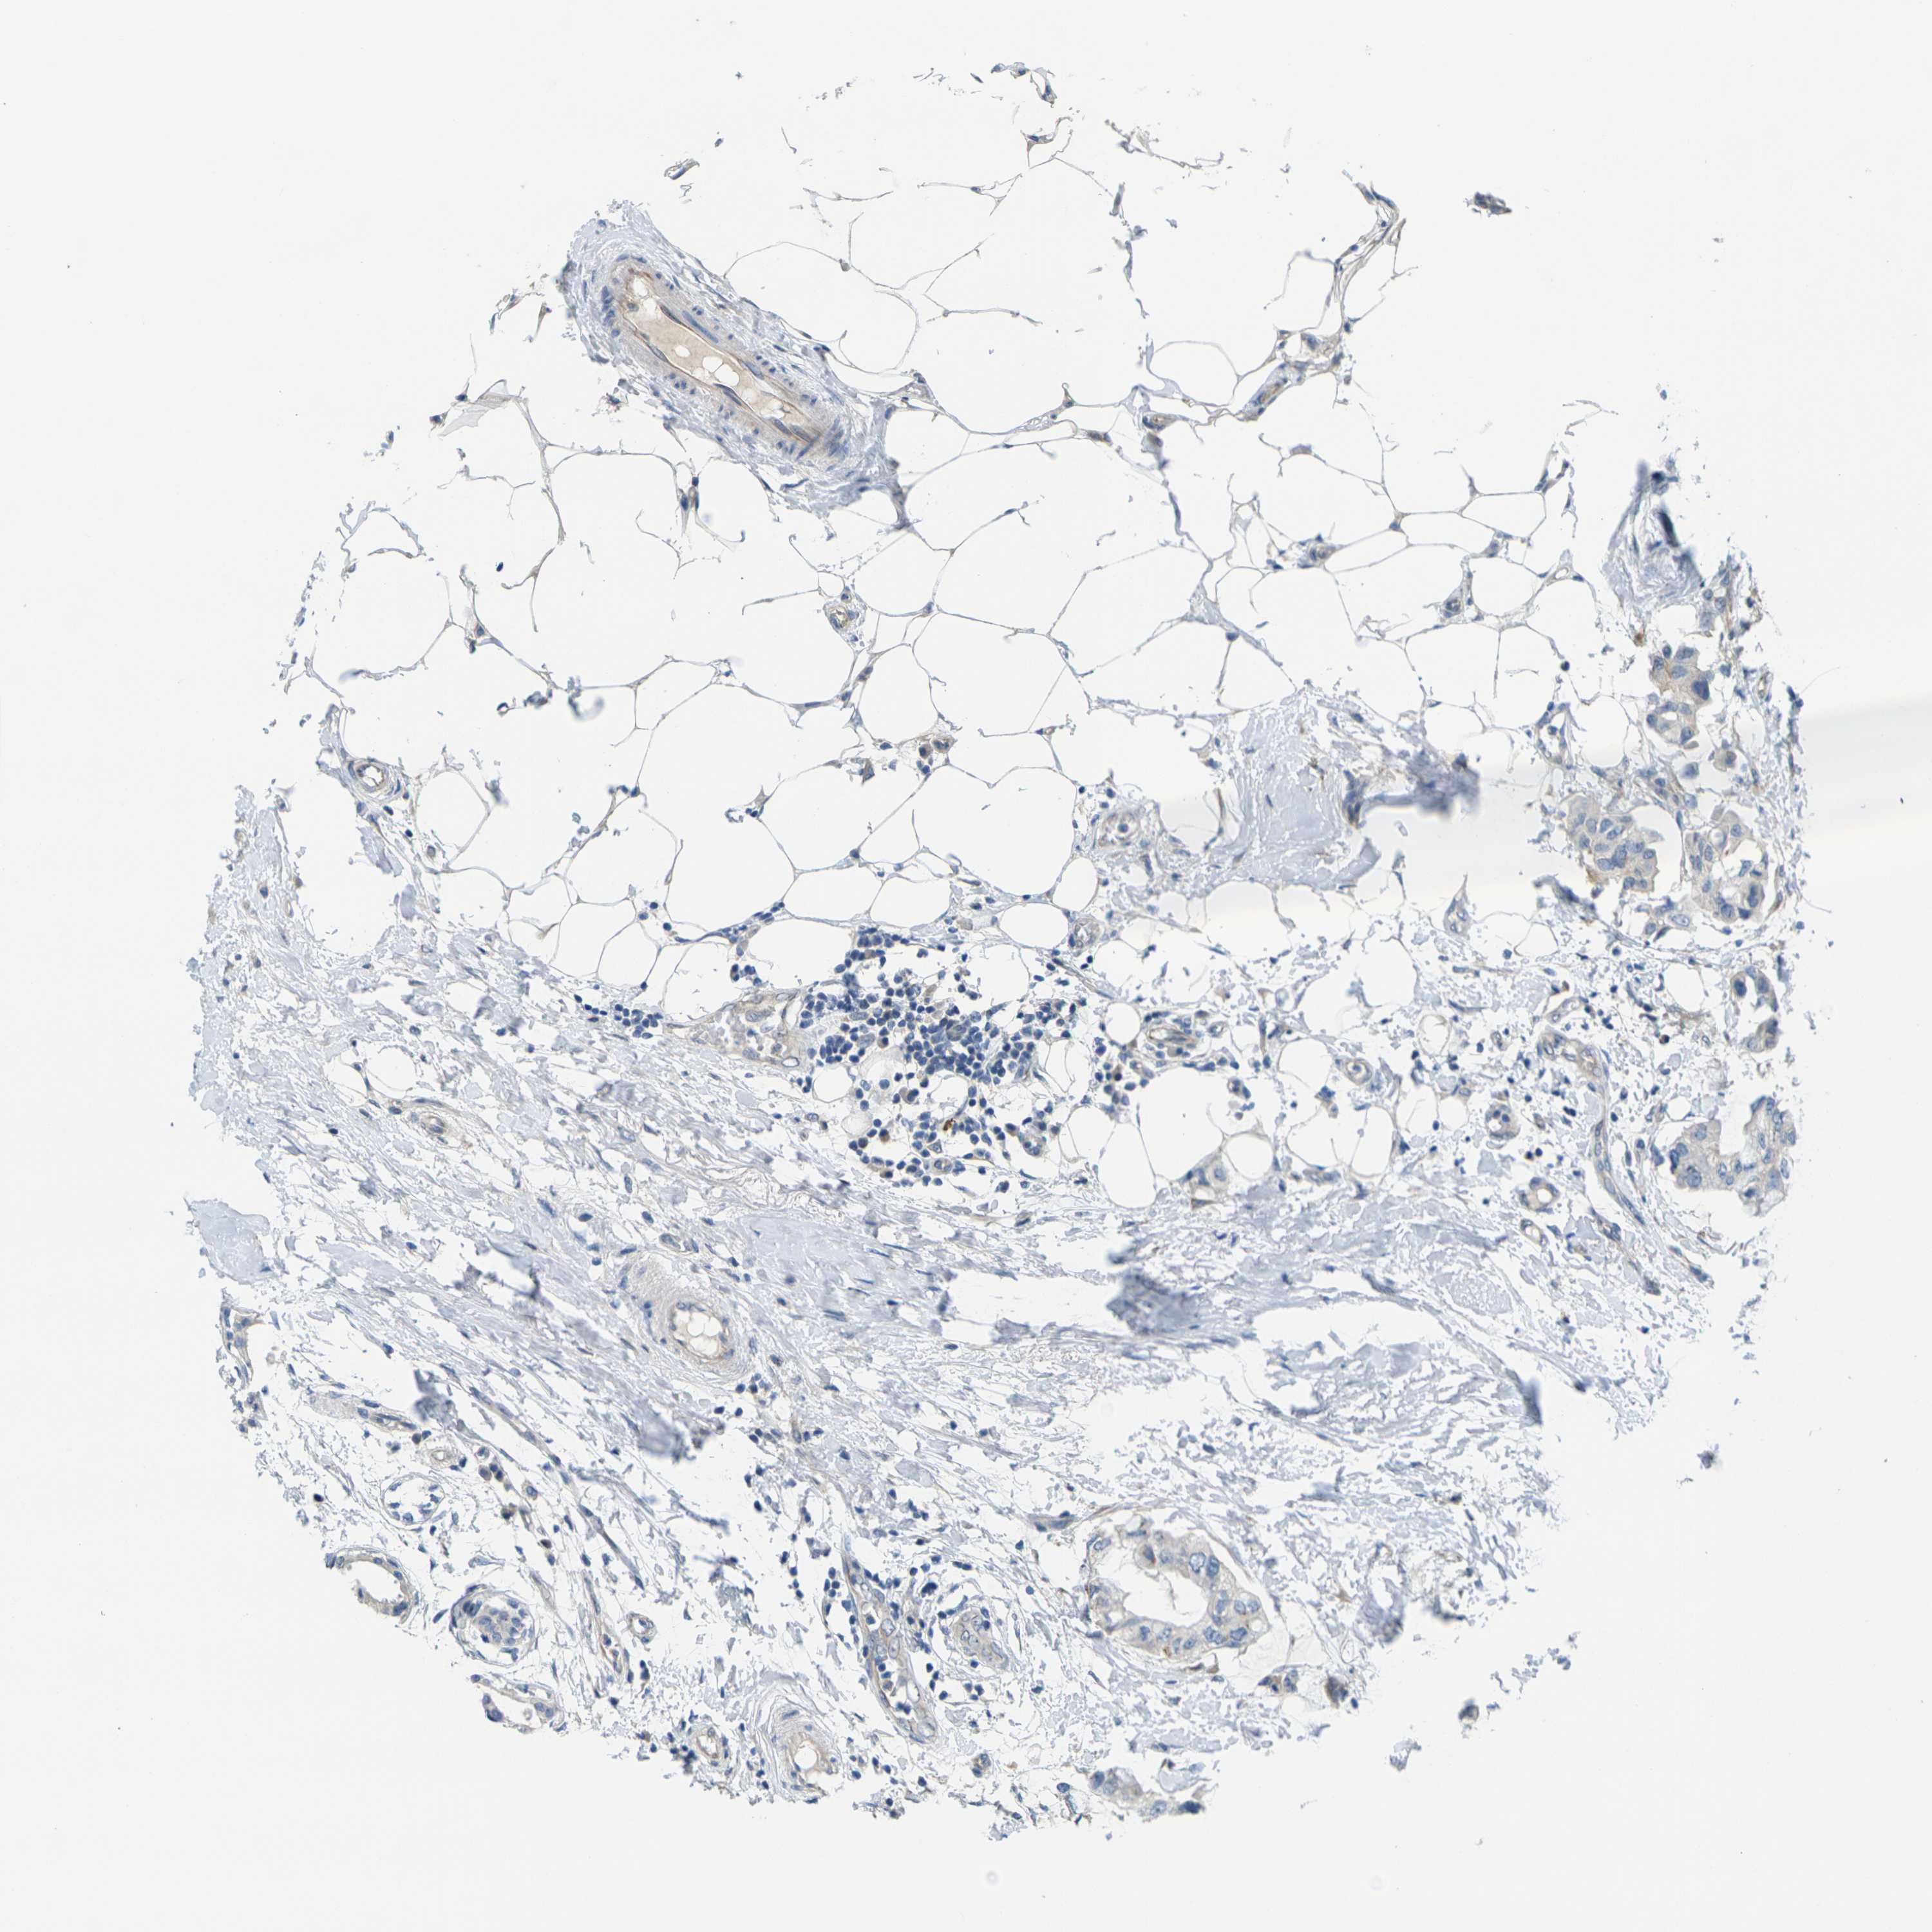

CANCER BREAST CANCER Show tissue menu

BRCA TCGA BRCA VALIDATION PROTEIN EXPRESSION

ANTIBODIES

AND

VALIDATION